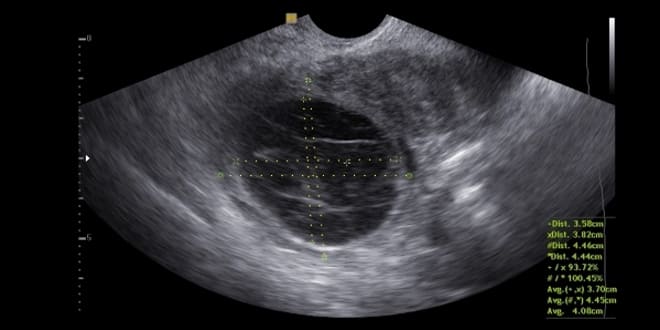

Фолликулярная

На ультразвуковом исследовании наблюдается однокамерное гипоэхогенное образование округлой формы. Стенки этого образования очень тонкие, а контуры четкие и ровные.

Фолликулярная киста содержит анэхогенную жидкость. Средний размер кисты составляет 10-13 см. Ткань придатка, расположенная позади кисты, выглядит нормальной и цельной.